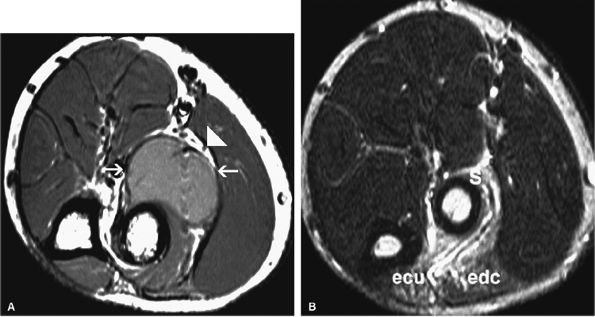

FIGURE 12.34 ● Posterior interosseous nerve syndrome secondary to bicipitoradial bursitis. (A) Axial PD-weighted image shows a markedly distended bicipital radial bursa (arrows) adjacent to the posterior interosseous nerve (arrowhead). (B) Axial fat-suppressed T2-weighted image demonstrates denervation edema and mild atrophy of the supinator (s), extensor carpi ulnaris (ecu), and extensor digitorum communis (edc) muscles in the proximal forearm.

|

FIGURE 12.35 ● Posterior interosseous nerve syndrome. Axial T1-weighted (A) and fat-suppressed T2-weighted (B) images at the proximal forearm show atrophy and edema of the supinator and extensor musculature. The extensor carpi radialis longus, which is not innervated by the posterior interosseous nerve, is not involved. s, supinator; edc, extensor digitorum communis; ecrb, extensor carpi radialis brevis; ecrl, extensor carpi radialis longus.